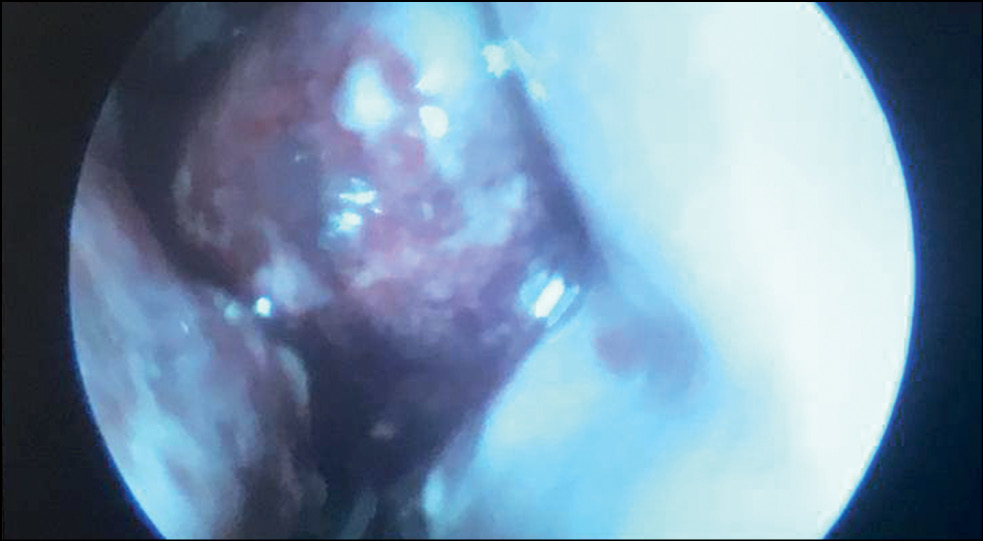

По данным эндоскопического исследования и КТ околоносовых пазух выполнена диагностическая пункция правой верхнечелюстной пазухи, диагностирован острый гнойный одонтогенный правосторонний гаймороэтмоидит. В этот же день с целью санации первичного септогенного очага выполнены радикальная операция на правой верхнечелюстной пазухе по Колдуэллу–Люку с наложением риностомы через нижний носовой ход (рис. 3), вскрытие клеток решётчатого лабиринта справа. При выполнении операции выявлен некроз слизистой оболочки пазухи, получено гнойное отделяемое. Пазуха дренирована поливинилхлоридной трубкой через нижний носовой ход. Материал отправлен на бактериологическое исследование флоры и определение чувствительности к антибиотикам.

Рис. 3. Тот же пациент. Эндоскопическая картина: общий и нижний носовой ходы сужены за счёт выраженного отёка нижней носовой раковины. Нижняя носовая раковина отёчна, гиперемирована, с признаками бактериальной инфекции, подслизистых кровоизлияний и тромбоза.